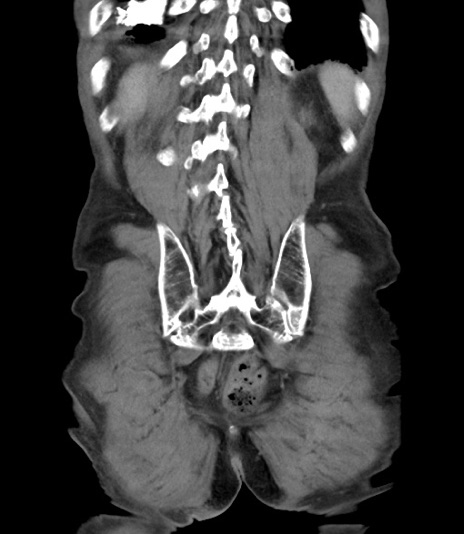

症例3(冠状断像)

【症例】 70歳代男性

【主訴】右鼠径部腫瘤、疼痛

【既往歴】膀胱癌にて膀胱全摘、両側尿管皮膚瘻